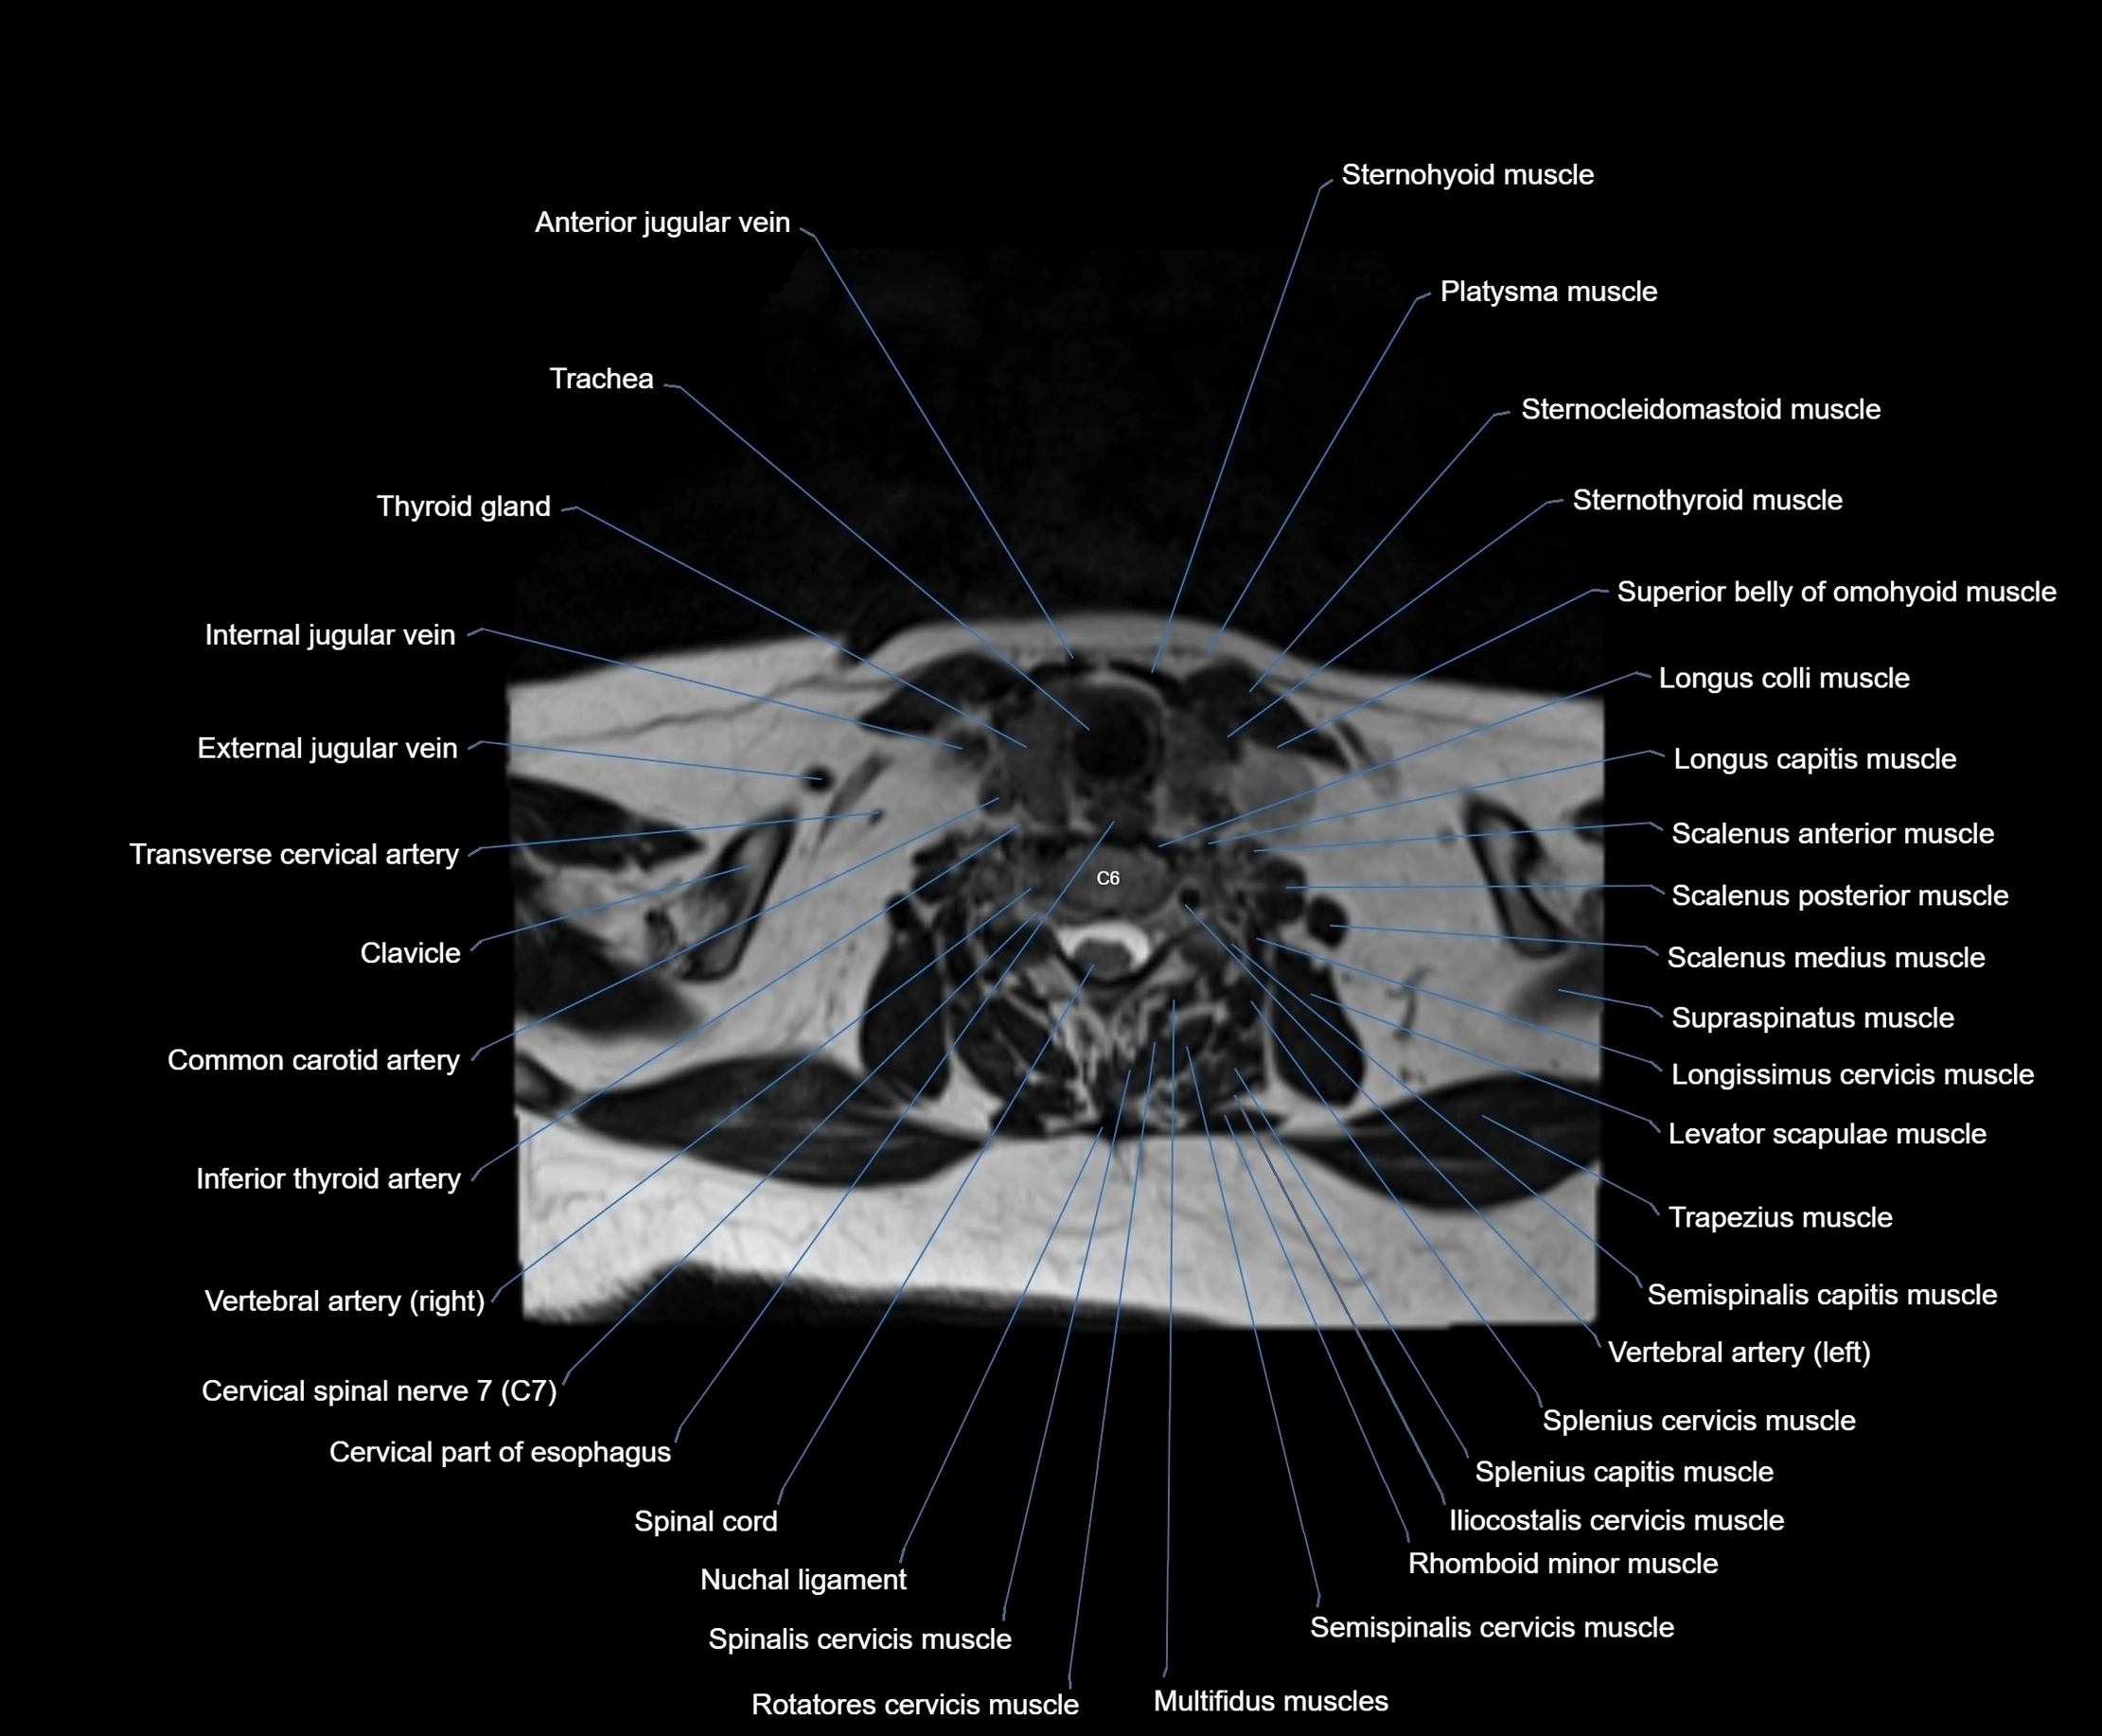

- Anterior jugular vein

- Cervical part of esophagus

- Cervical spinal nerve 7 (C7)

- Clavicle

- Common carotid artery

- External jugular vein

- Iliocostalis cervicis muscle

- Inferior thyroid artery

- Longissimus cervicis muscle

- Longus colli muscle

- Multifidus muscles

- Nuchal ligament

- Platysma muscle

- Rotatores cervicis muscle

- Scalenus anterior muscle (Anterior scalene muscle)

- Scalenus medius muscle (middle scalene muscle)

- Scalenus posterior muscle (Posterior scalene muscle)

- Semispinalis capitis muscle

- Semispinalis cervicis muscle

- Spinal cord

- Spinalis cervicis muscle

- Splenius capitis muscle

- Splenius cervicis muscle

- Sternocleidomastoid muscle

- Sternohyoid muscle

- Sternothyroid muscle

- Superior belly of omohyoid muscle

- Supraspinatus muscle

- Thyroid gland

- Trachea

- Transverse cervical artery

- Trapezius muscle